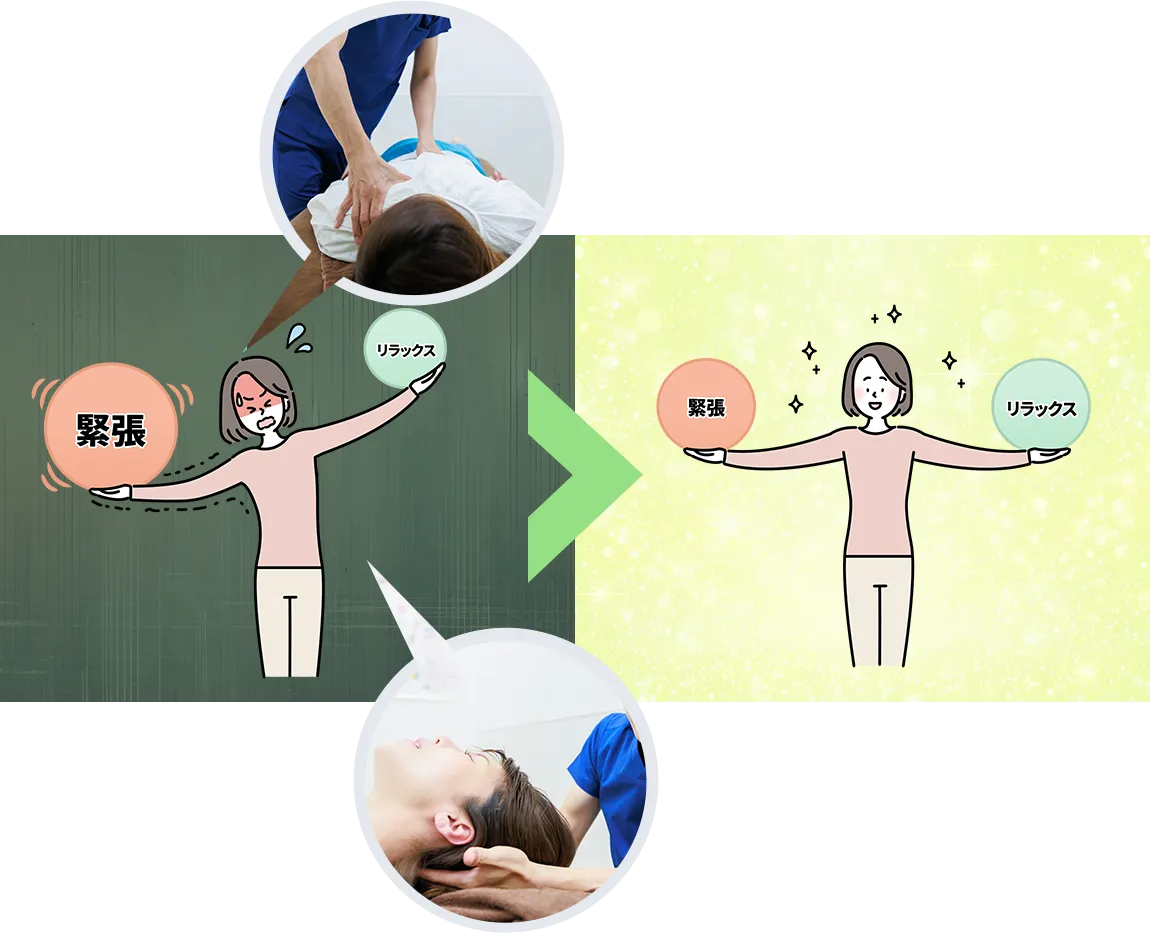

整骨院の最初のイメージでは、マッサージや電気治療で、少しでも今の症状が改善すればいいかなと思っていたのですが…

自分の姿勢や癖を指摘してもらいエビデンスに基づいた説明、施術をしてもらうことで納得し改善も実感できました。

自分の特徴や身体の事を知るのは面白くセルフケアの方法も教えてもらえ楽しみながら通うことが出来ました。